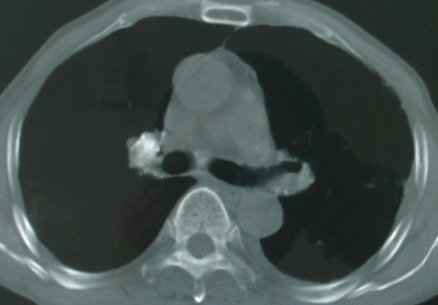

以下是引用医影拾贝在2008-6-3 18:48:00的发言:[br]双上肺弥漫性小结节影,纵隔窗内钙化淋巴结影,考虑血播性tb可能性较大,不除外肺ca可能

以下是引用卜一在2008-6-3 19:33:00的发言:[br]双肺结节,以双上肺分布为多,期间搀杂片状致密影及索条致密影。考虑:继发性肺结核伴血型播散可能性大。不除外肺泡ca的可能!另:椎体退变!

以下是引用panyishengct在2008-6-3 21:09:00的发言:[br]双上肺弥漫性小结节影,纵隔窗内钙化淋巴结影,考虑矽肺或/和tb可能性较大,不除外肺ca可能。腰椎考虑退变。 [br][br]